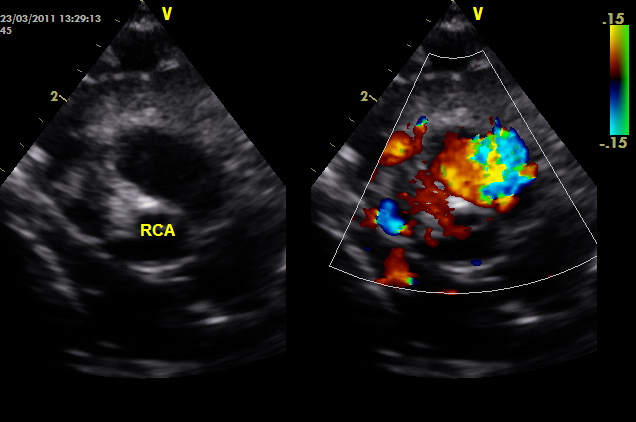

Υπερηχογράφημα (ECHO): φυσιολογική βασική ανατομία, φυσιολογικές διαστάσεις και λειτουργικότητα (συστολική και διαστολική λειτουργία, ελέγχθησαν και με ιστικό Doppler πέραν του συνήθους ελέγχου). Παρακάτω απεικονίζονται τα στεφανιαία. Ελέγχθηκε η έκφυση όχι μόνο με 2D, αλλά και με απεικόνιση της στεφανιαίας ροής με color Doppler (ασυνήθης πρακτική για παιδιά, θα εξηγηθεί ο λόγος στη συνέχεια).